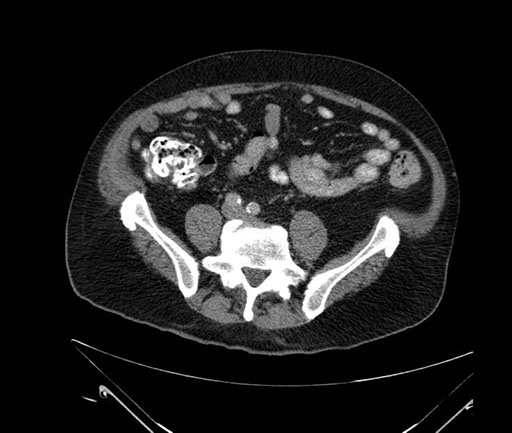

Whipple (pancreaticoduodenectomy) [case 7]

Imaging Analysis

Look through the patient's CT scan to identify any areas of concern for the necessary procedure.

Based on your CT findings, which issue(s) would give reason for "planned slowing down moment(s)" in this case?

Considering a standard Whipple procedure, what step(s) of the operation would you do differently in this case?